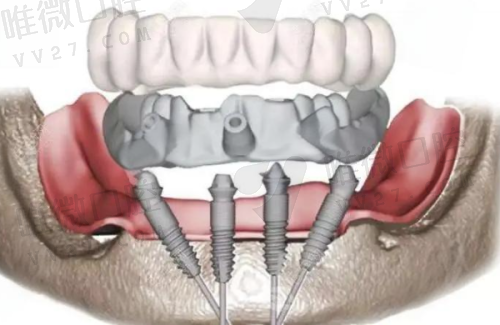

以当前2024年集采价为参考,目前单颗种植牙价格区间大致为3980元起至8980元起。根据不同品牌、牙体情况、种植方式(是否采用即刻种植、是否需要植骨等)费用略有差异。

- 半口种植牙:通常12800元起至55000元左右

- 全口种植牙:从25600元至110000元不等